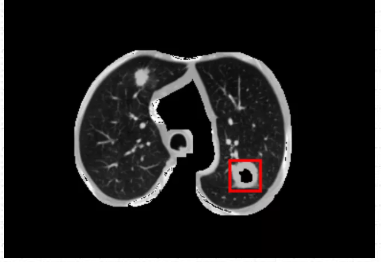

箭头指的地方可看见检测结果,可以说利用ModelArts平台训练出来的肺结节检测模型检测效果是很棒的。(直接看太小的话,可以点开图片放大看)

从最后实验的结果对比图来看,可以说利用ModelArts平台训练出来的肺结节检测模型检测效果是很棒的,虽然存在一定的肺结节病灶假阳性标记,但是这在小样本数据集的人工智能医疗检测中是会出现的情况。毕竟对于人工智能医疗检测模型来说,只用了300张标注图片就能达到这样的效果,真的让人感到惊喜。